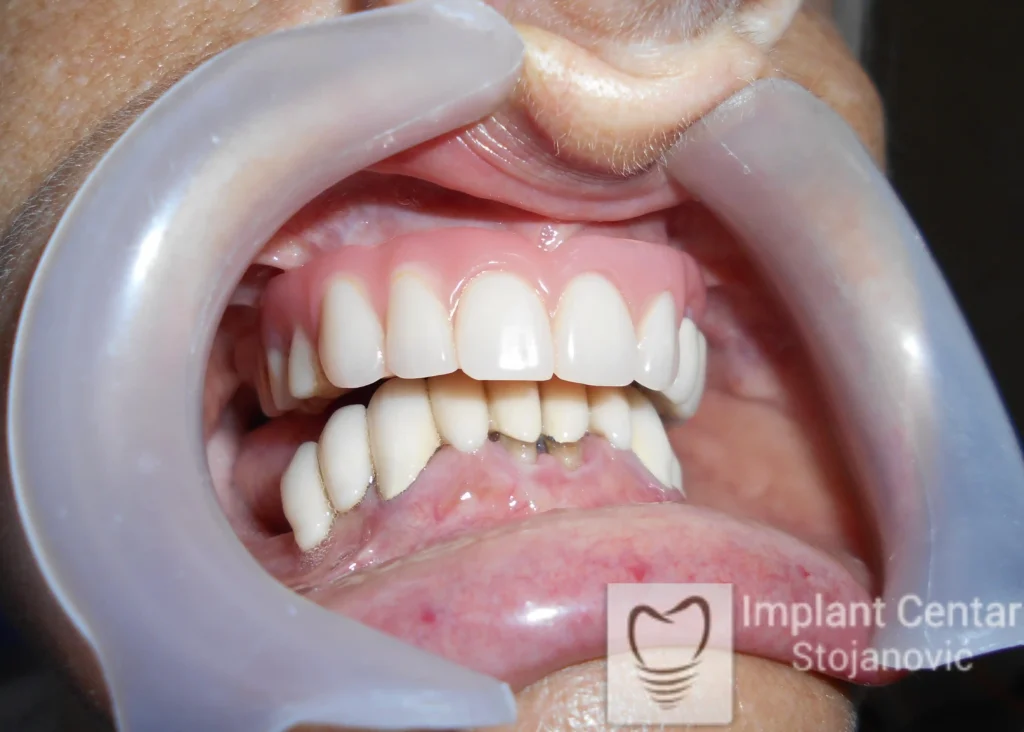

Po završetku perioda integracije, izrađeni su definitivni cirkonijum-keramički mostovi, čime je postignuta potpuna rekonstrukcija zagriza, kao i značajno poboljšanje estetike i oralne funkcije (slika 12, 13, 14 i 15).

Nakon završetka perioda integracije implantata, izrađeni su cirkonijum-keramički mostovi u gornjoj i donjoj vilici (slika 6.).